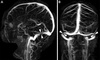

QUAIS OS ACHADOS DA RNM DA HIPERTENSÃO INTRACRANIANA IDIOÁTICA?

A

How well did you know this?

POSSÍVEIS ACHADOS DE IMAGEM NA RNM da hii?

inespecíficos - sela turcica vazia - dilatação e tortuosidade do nervo optico com achatamento do globo - realce do disco - estenoses do seio transverso